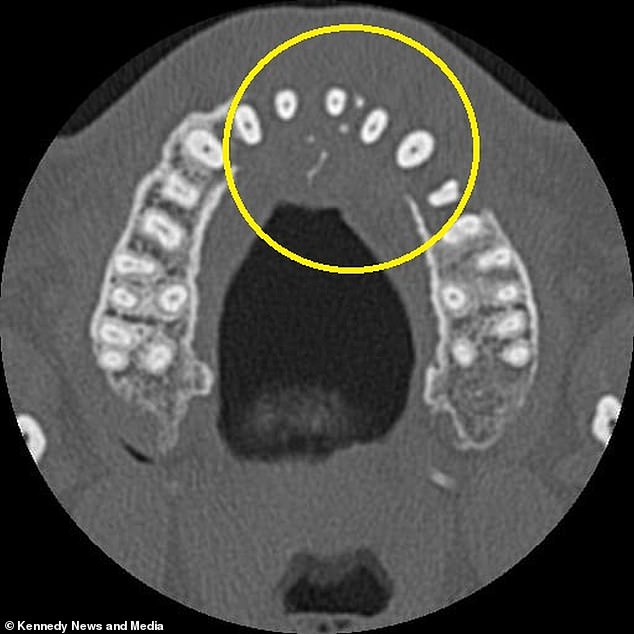

The diagnosis came as a devastating blow: stage two diffuse large B-cell lymphoma (DLBCL), a fast-growing form of non-Hodgkin lymphoma. CT scans showed the tumor had eroded his upper jawbone and begun spreading to his neck. 'If I had ignored the toothache, it could have gotten much worse,' Vieira said. His symptoms had included difficulty blowing his nose without pain and the appearance of a small, hard lump near his right nostril—details he initially dismissed as unrelated.